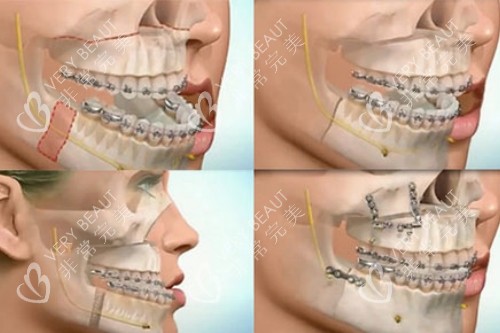

何医生团队用三维CT和咬合模型分析我的骨骼问题,明确告诉我:“单纯正畸改善有限,双鄂截骨才能让上下颌骨回归正确位置。”

进手术室前,护士反复核对方案,麻醉师轻声安抚情绪。

何医生拿着标记笔在我脸上画线时,突然开玩笑:“今天之后,你就能实现‘侧颜自由’啦!”这句话莫名让我放松下来。

何医生查房时总会多待5分钟,检查咬合板位置,叮嘱我“别偷吃硬的”!